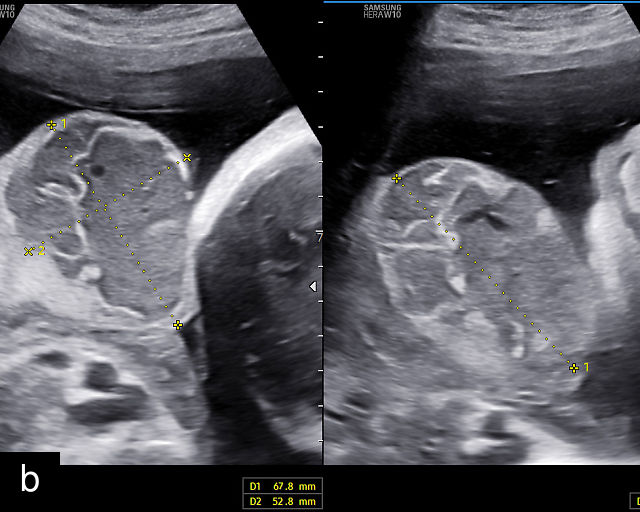

Placental chorioangiomas

Chorioangiomas are benign tumors of the placenta, arising from chorionic tissue.141 These tumors consist of capillaries and cellular stroma in varying proportions.141,142 While clinical diagnosis of chorioangiomas is relatively uncommon, histopathological analysis reveals their presence in approximately 1% of all placentas.142 Most chorioangiomas identified on prenatal ultrasound are incidental findings during routine examination and are typically those that are larger in size.9 Consequently, the prevalence of chorioangiomas detected sonographically is significantly lower than the prevalence observed in pathological examinations of placentas. More rarely, chorioangiomas may be detected during ultrasound evaluation for polyhydramnios or FGR.143 Large chorioangiomas (greater than 4 cm in diameter) are thought to occur in approximately 1 : 3500–1 : 9000 pregnancies (0.01–0.03%).141 These larger chorioangiomas may be associated with significant complications, including polyhydramnios, fetal hydrops, fetal anemia, FGR and even fetal death.9,141,143,144,145 A systematic review reported a fetal death rate of 8.2% in cases of prenatally diagnosed chorioangioma in which no intervention was performed.145 Additionally, preterm birth before 37 weeks occurred in 34.1% of these pregnancies (95% CI, 21.1–48.3%). The study also found that 24.0% of infants (95% CI, 13.5–36.5%) were born small-for-gestational age.145 The most important predictor of outcomes was the size of the tumor.145

The typical sonographic appearance of a chorioangioma on grayscale ultrasound is a well-circumscribed mass arising from the fetal surface of the placenta, protruding into the amniotic cavity, and distinctly separate from the placenta (Figure 12; Video 7). These tumors are most commonly located near the umbilical cord insertion site on the placenta. Sonographically, they may appear hypoechoic or hyperechoic and are often heterogeneous, with possible calcifications, hemorrhage or infarction visible within the mass.9 The appearance of these masses may change over time.141 Color flow Doppler imaging typically reveals vascularity within the tumor, showing low-resistance vessels and arteriovenous shunts (Figure 12c–e; Video 7).9 These shunts are believed to contribute to fetal complications such as high-output cardiac failure, anemia and hydrops.141 Three-dimensional ultrasound may be helpful in assessment of the mass.146 Importantly, the differential diagnosis includes placental hemorrhage, and color flow Doppler is essential to assist in making the diagnosis.

12

Grayscale (a,b), color Doppler (c,e) and power Doppler (d) images of chorioangiomas, showing heterogeneous masses protruding from the placental surface.